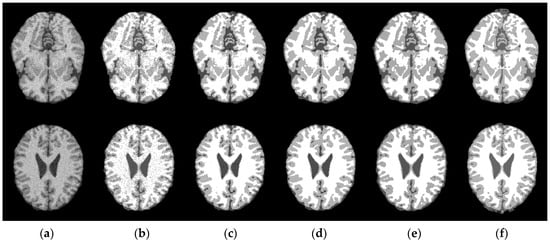

4.3. Effectiveness of RC_LCI